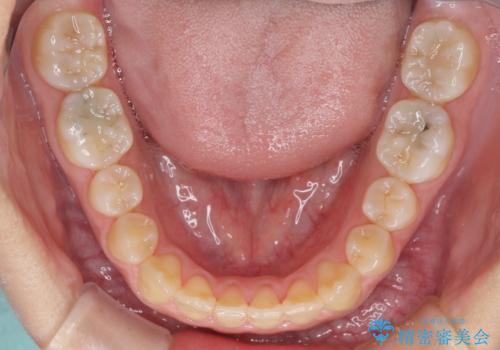

受け口で開咬を急速拡大装置とインビザラインで改善 欠損部分はインプラントにて補綴治療

矯正治療が終わるタイミングに合わせてインプラントの埋入を行っていたので、矯正治療を終了すると同時にセラミック補綴治療を行えました。

インビザラインの装着時間が不十分であったので、治療期間は長期間となりました。